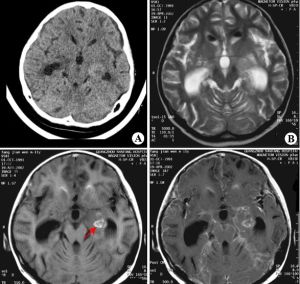

本型較少見。1907年,Lacount首先報告,它是新生隱球菌侵犯腦實質後形成的一種炎症性肉芽腫病變,稱為隱球菌性腦肉芽腫,常好發於大腦、小腦、腦幹的延髓部位。臨床症狀與體徵隨肉芽腫病變的部位和範圍不同以及是否合併腦膜損害而異,位於腦實質內的肉芽腫,其症狀、體徵與腦瘤相似,臨床上難以鑑別,腦脊液壓力常增高,細胞數輕度增多,墨汁塗片及真菌培養可發現隱球菌,但陽性率低。CT、MRI檢查、腦血管造影、腦室造影、腦超聲檢查等,均可能發現腦部占位性病變,術前常難於確診,須行開顱探查術,術中可見肉芽腫表現為魚肉樣腫塊,病理切片發現隱球菌可確診。

隱球菌腦膜炎囊腫型

本型為隱球菌刺激腦膜形成囊腫所致,表現為顱內占位性病變。可有頭暈、頭痛、耳鳴、聽力下降、出汗、嘔吐、走路不穩、單側偏癱等症狀。頸內動脈造影可顯示顱內占位性病變區,開顱手術可見蛛網膜明顯增厚,蛛網膜腔內可形成單個或多個囊腫,囊腫內為無色透明的液體。組織病理檢查顯示囊壁由纖維結締組織構成,並有淋巴細胞、大單核細胞及多形核細胞浸潤,可有少數異物巨細胞存在,囊腔內充滿頻寬闊莢膜的新生隱球菌菌體。檢查